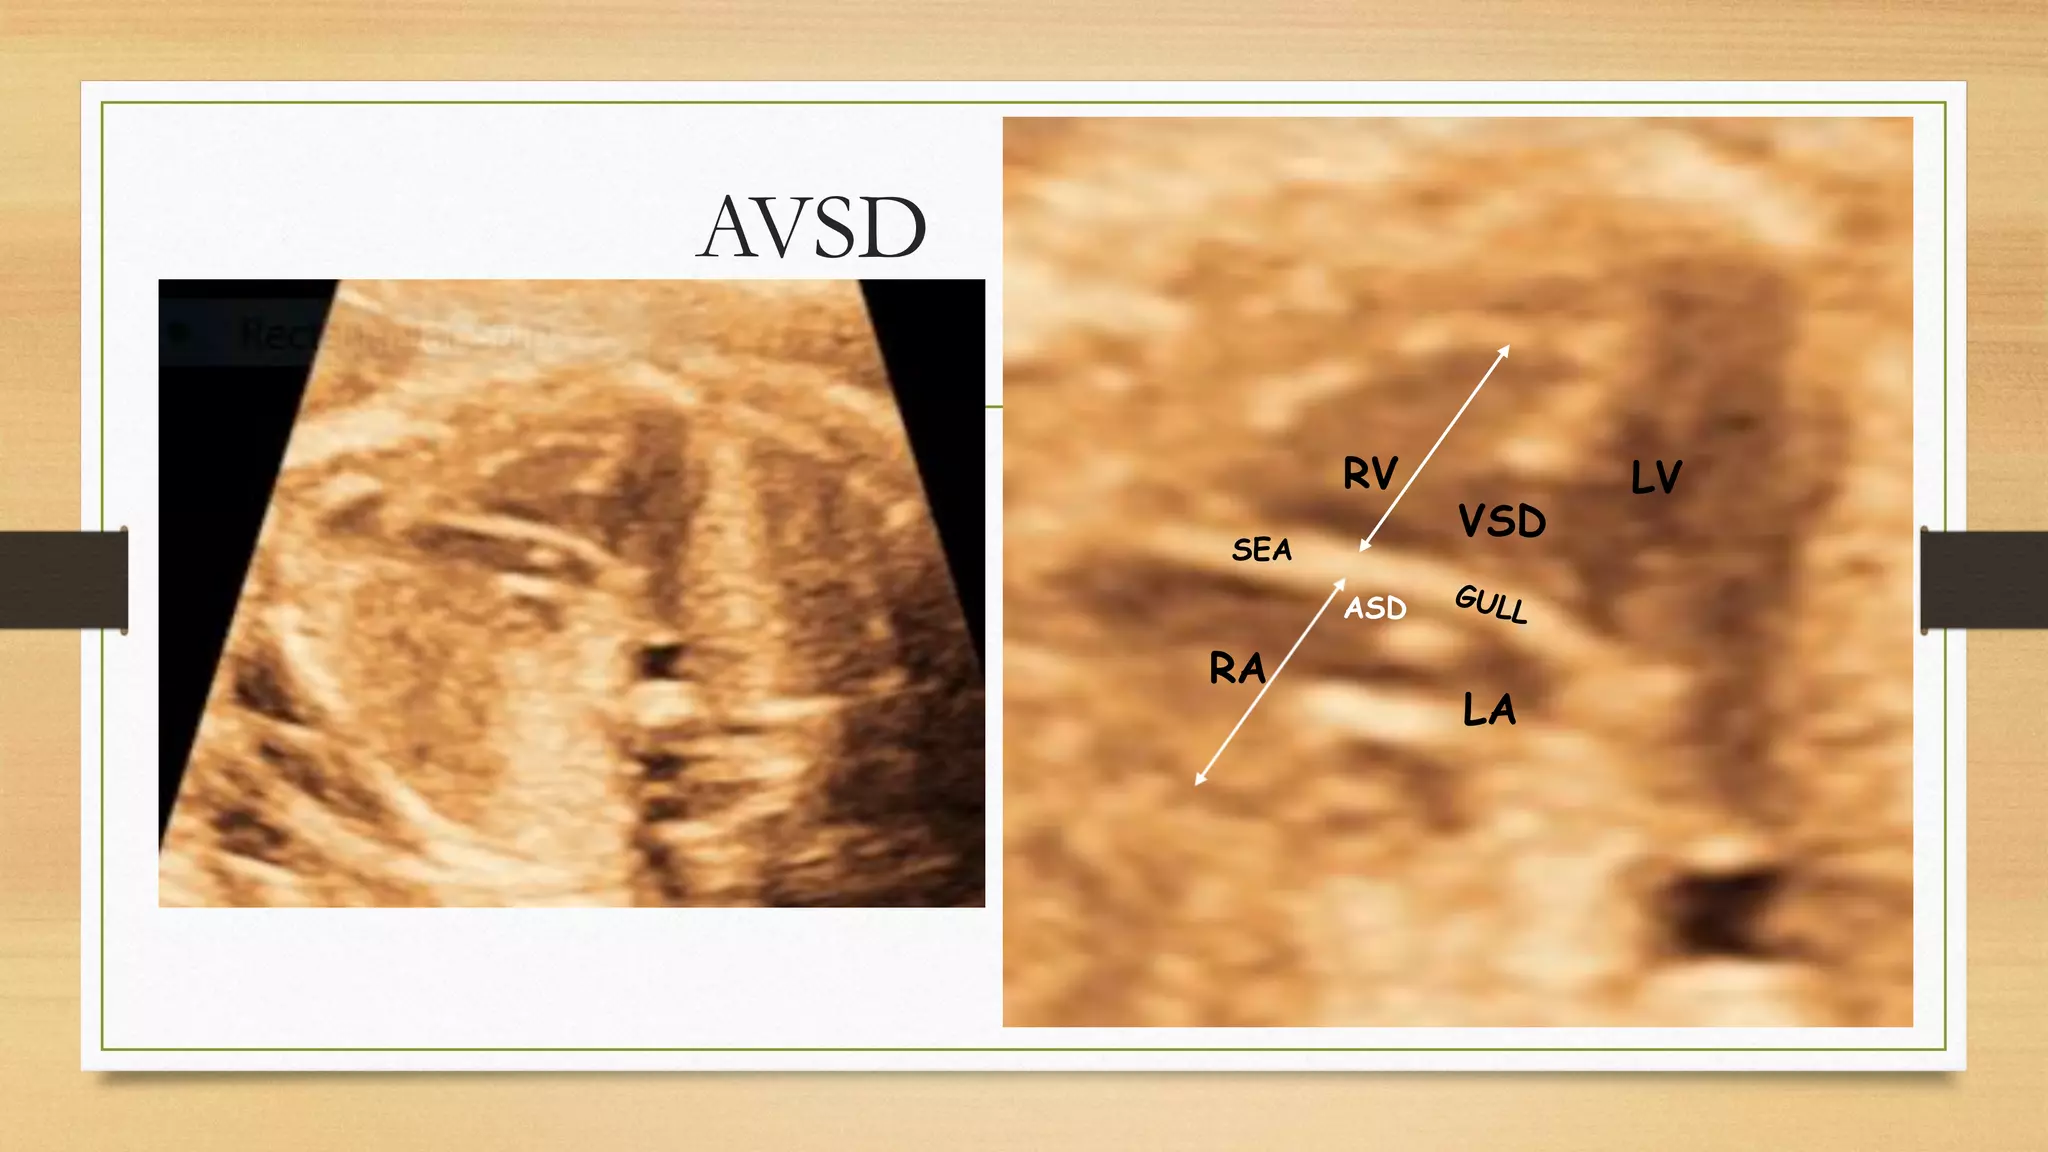

Fetal echocardiography

Atiro-ventricular valve should be seen in apical 4 chamber view ( may not be seen in basal and lateral

4 C view) to look for loss of offset, both valve At one level like bird wing, seagull sign.

Right atrial length is 40% of right ventricular length, and ratio is 40%, This ratio is increases and RA

may be equal to right ventricle length. Color Doppler depict central jet of regurgitation.

AVSD

RV

RA

LA

LV

VSD

ASD

SEA